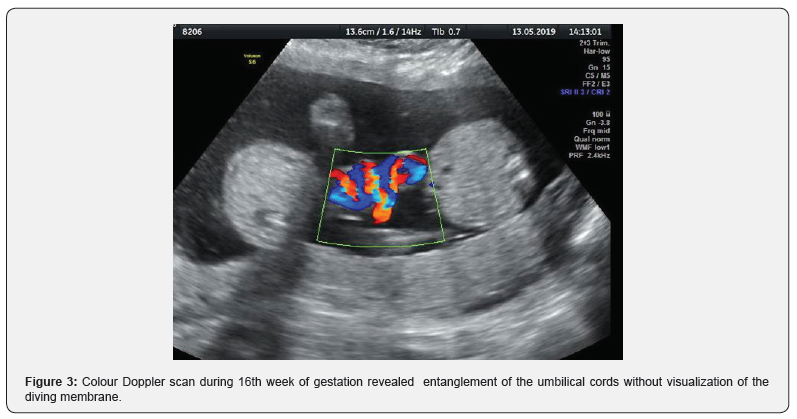

Ultra sonographic scan during 16th week of gestation revealed normal growth for both embryos, without visualization of the diving membrane. Entanglement of the umbilical cords (Figure 3). Diagnosis of fetal demise during routine ultrasound during 29th week of gestation without any previous complications concerning fetal growth or Doppler assessment. Weekly ultrasonography performance of the other embryo followed by measurement of MCA (Middle Cerebral Artery) maximum velocity index as predictor rate of fetal anemia. MCA v max during 30th week of gestation above 95th centile